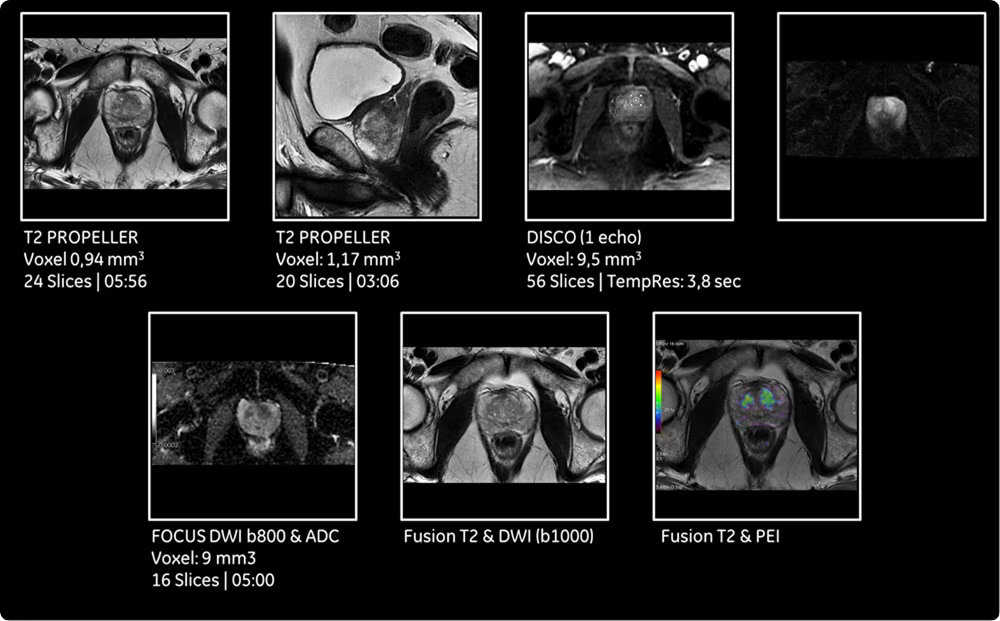

| DWI (диффузионно-взвешенная МРТ) | Оценка диффузии воды в тканях для ранней диагностики ишемии, высококлеточных опухолей и воспалительных изменений. |

| Целотельные протоколы | Обследование всего тела для онкологического поиска, стадирования и мониторинга эффективности терапии. |

| Динамические контрастные исследования | Серийное сканирование после введения контрастного препарата для оценки васкуляризации и характеристик образований. |